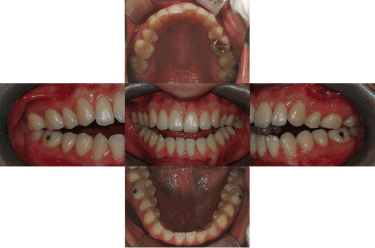

Before treatment, all six patients had ICR and an open bite caused by counterclockwise rotation of the mandible (Figure 4). The patients recovered a normal relationship in the anterior region via appropriate treatment of TMJ disorder accompanied by orthognathic surgery and orthodontic treatment. During follow-up, three patients intermittently complained of having symptoms of TMJ disorder. These symptoms were relieved by taking precautions and consulting their dentists, without the need for special treatment. One patient had a relapse of TMJ disorder due to a head injury and accordingly received an intra-articular injection of anti-adhesive agents. All six patients showed no signs of either a relapse of ICR or an open bite during radiographic and clinical examinations (Figure 5).

Figure 5. Final intra-oral photo: 23.27 months after orthognathic surgery. There is no open bite recurrence.